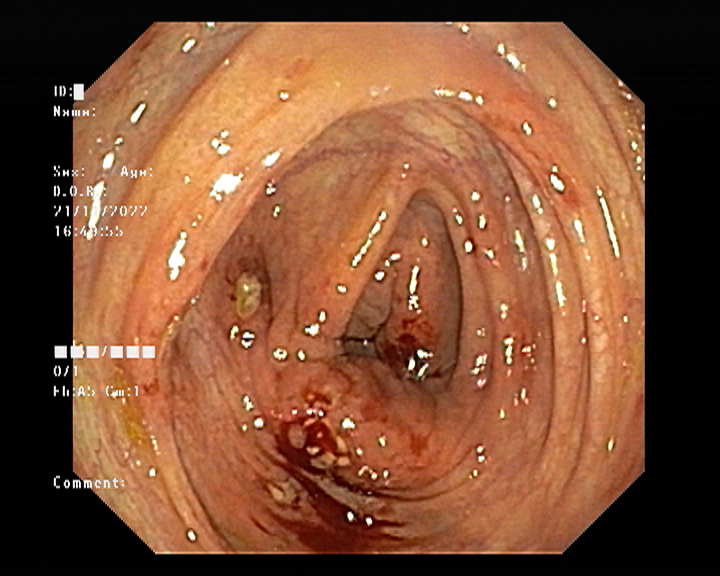

Endoscopy and colonoscopy are safe and accurate procedures used to directly examine the digestive tract and detect the root cause of chronic acidity, GERD, abdominal pain, bleeding, and bowel irregularities. These minimally invasive tests help identify ulcers, inflammation, infections, polyps, strictures, and early cancerous changes.

At Sapphire Gastroenterology Center, modern endoscopic equipment ensures precise diagnosis and, when required, therapeutic intervention during the same procedure. Based on findings, targeted treatment plans are created, including medication, diet guidance, and preventive strategies. Early diagnosis through endoscopy and colonoscopy plays a crucial role in preventing serious complications and improving long-term digestive health.